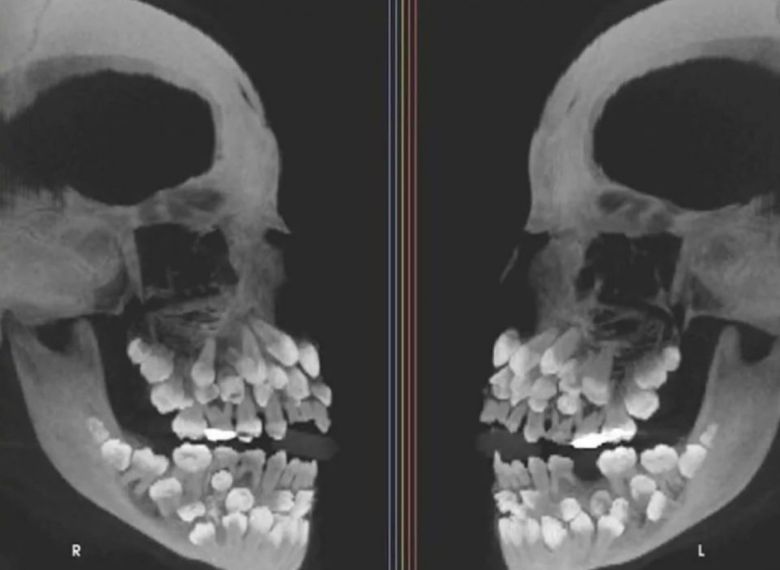

소녀의 치아는 총 81개로 세계적으로 드문 사례다.

15일(현지시간) VN익스프레스 등 외신에 따르면, 브라질 미나스제라이스주에 사는 소녀는 유치를 뽑기 위해 치과를 찾았다가 엑스레이 사진을 보고 충격 받았다. 아직 나지 않은 치아를 포함해 모두 81개가 있었기 때문이다.

그런데 이 소녀는 유치 18개에 영구치 32개, 과잉치가 31개였다.

소녀를 진료한 병원 연구진은 “이런 상태는 ‘다발성 과잉치증’”이라며 “과잉치는 보통 한두 개 생기는데, 30개가 넘는 경우는 거의 없다”고 설명했다.

연구진은 CT 등 정밀 영상을 통해 치아 위치와 주변 조직과의 관계를 확인했고, 유전적 원인을 찾기 위해 유전자 검사도 병행했다.